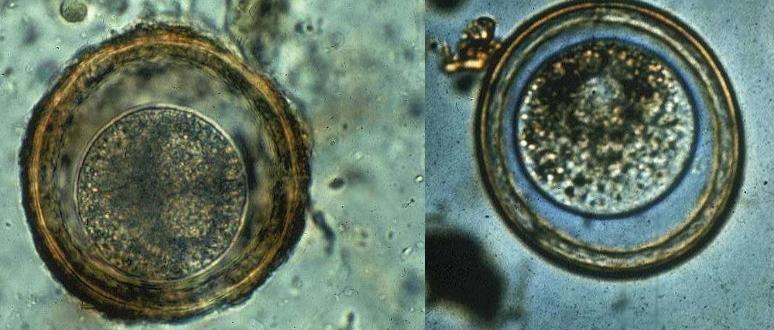

1. This is an egg of what?

2. What animal species houses this parasite?

3. What are some specific characteristics of the egg?

1. Ascaris suum

2. Pig

3. Egg characteristics:

1. Thick shell

2. Rough outer covering with projections

3. Single cell inside

4. Rust brown

5. STICKY!